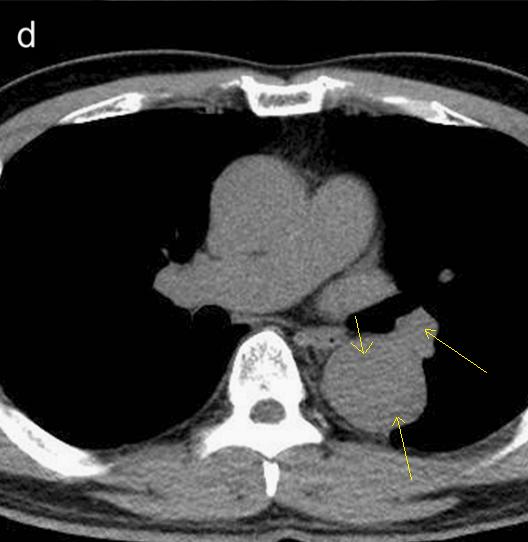

CT这么模糊,平扫怎么看主动脉夹层?

不着急!仔细看,血管里面的“血液”居然钙化了!这叫血管钙化内移,要警惕主动脉夹层!有研究发现,血管钙化内移诊断动脉夹层的特异性高达90%。

用箭头标记了,并且是增强CT,这是主动脉夹层!